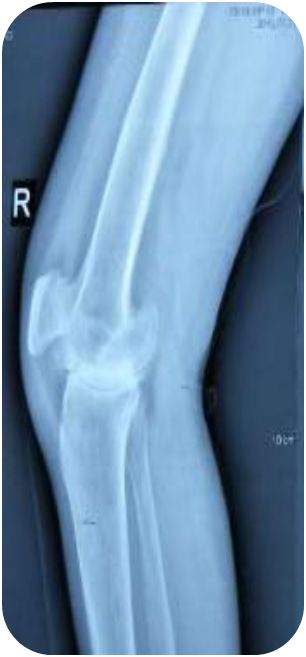

患者出院后也一直门诊坚持治疗,每月2次,期间行关节腔注射玻璃酸钠2次润滑关节,至2019年5月予患者复查右膝关节X片,患者膝关节间隙较前明显清晰,患者膝关节疼痛明显减轻,基本无疼痛,行走时感少许酸软无力,膝关节活动度较前明显增大,从原先腘窝下距离床面三拳明显减少到一拳,后患者陆续又行双肩、双肘关节小针刀松解术,疼痛也得到明显改善。

患者治疗前后膝关节X线片对比